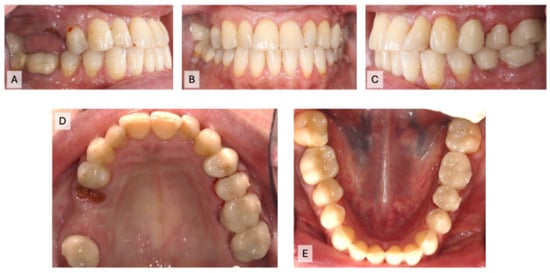

The patient was seen for visit 1 for transitional aligners 1–3 (3 weeks). At visit 2, an IPR of 0.3 for mandibular anterior teeth was performed, and aligners 4–15 (12 weeks) were provided. In visit 3, aligners 16–27 (12 weeks) were given, followed by 28–39 (12 weeks) at visit 4. The patient was instructed to change aligners weekly. Teeth tracking was satisfactory at each visit, with no emergency incidents or attachment breakage, and aligners adapted well to the M-PCA (Figure 10A–E).

Figure 10.

Intraoral photographs after orthodontic treatment: (A) right occlusion; (B) front occlusion; (C) left occlusion; (D) maxillary occlusion; (E) mandibular occlusion.